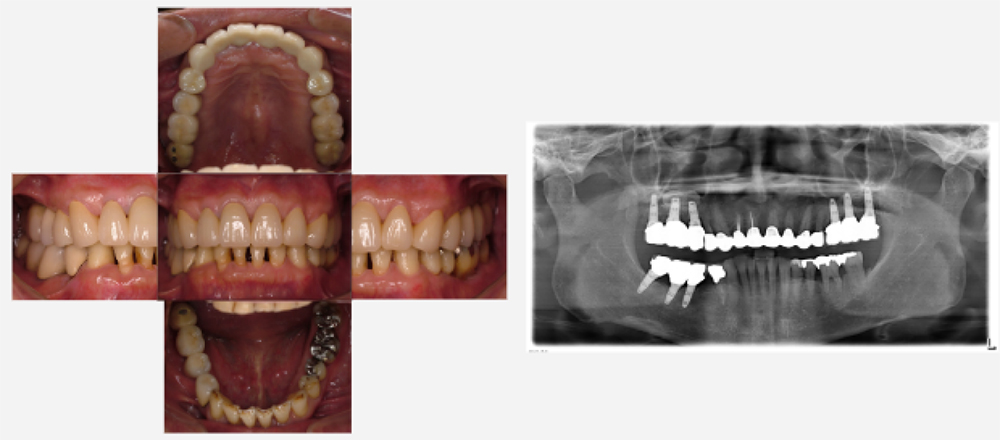

2008年03月 初診時

2008年06月 歯周基本治療終了後

2016年6月 約4年経過

2023年12月 上顎残存歯

最終補綴処置終了後 約2年経過

| 治療内容 | 重度歯周病・インプラント・矯正治療 |

|---|---|

| 患者様の年齢 | 52歳 |

| 患者様の性別 | 男性 |

| 治療期間 | 初診時より4年 |

| 治療回数 | 矯正治療・歯周治療・インプラント治療合わせて130回程度 |

| 治療費用 | インプラント:約450万円/歯周病:15万円 矯正:15万円/補綴治療:110万円 |

| 治療で得られるメリット |

|

| 治療する際に起こる リスク・副作用 |